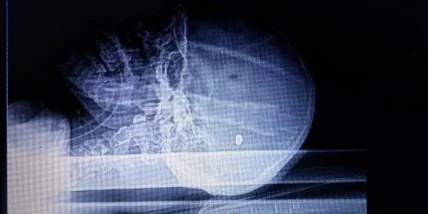

"Пятерых раненых в результате обстрела "промки" под Авдеевкой доставили в Днипро военным вертолетом. Двое бойцов переданы команде Сергея Рыженко. Один солдат находится в крайне тяжелом состоянии. Через 10 минут после обследования были получены рентгеновские снимки. Военные врачи стабилизировали 19-летнего Женю (не ВСУ). Еще один военнослужащий с осколочными ранениями находится в сознании на дополнительном исследовании. Троих тяжело раненных скорая помощь медицины катастроф повезла в военный госпиталь", - написала Губа.